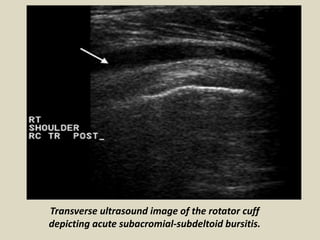

Transverse ultrasound image of the rotator cuff

depicting acute subacromial-subdeltoid bursitis.